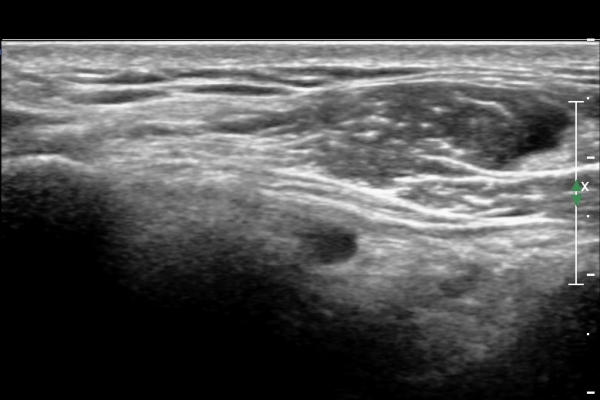

¿À±¸µ¹±â°ßºÀÀδë Á¾´Ü¸é°Ë»ç¿¡¼­ ÀÎ´ë ½ÉÃþ¿¡ ¼ö¾×Àú·ù°¡ °üÂûµÊ(»çÁø 1, 2)

ÀÌ´Â Ãæµ¹ÁõÈıºÀ» ¾Ï½ÃÇÏ´Â ¼Ò°ßÀÓ.